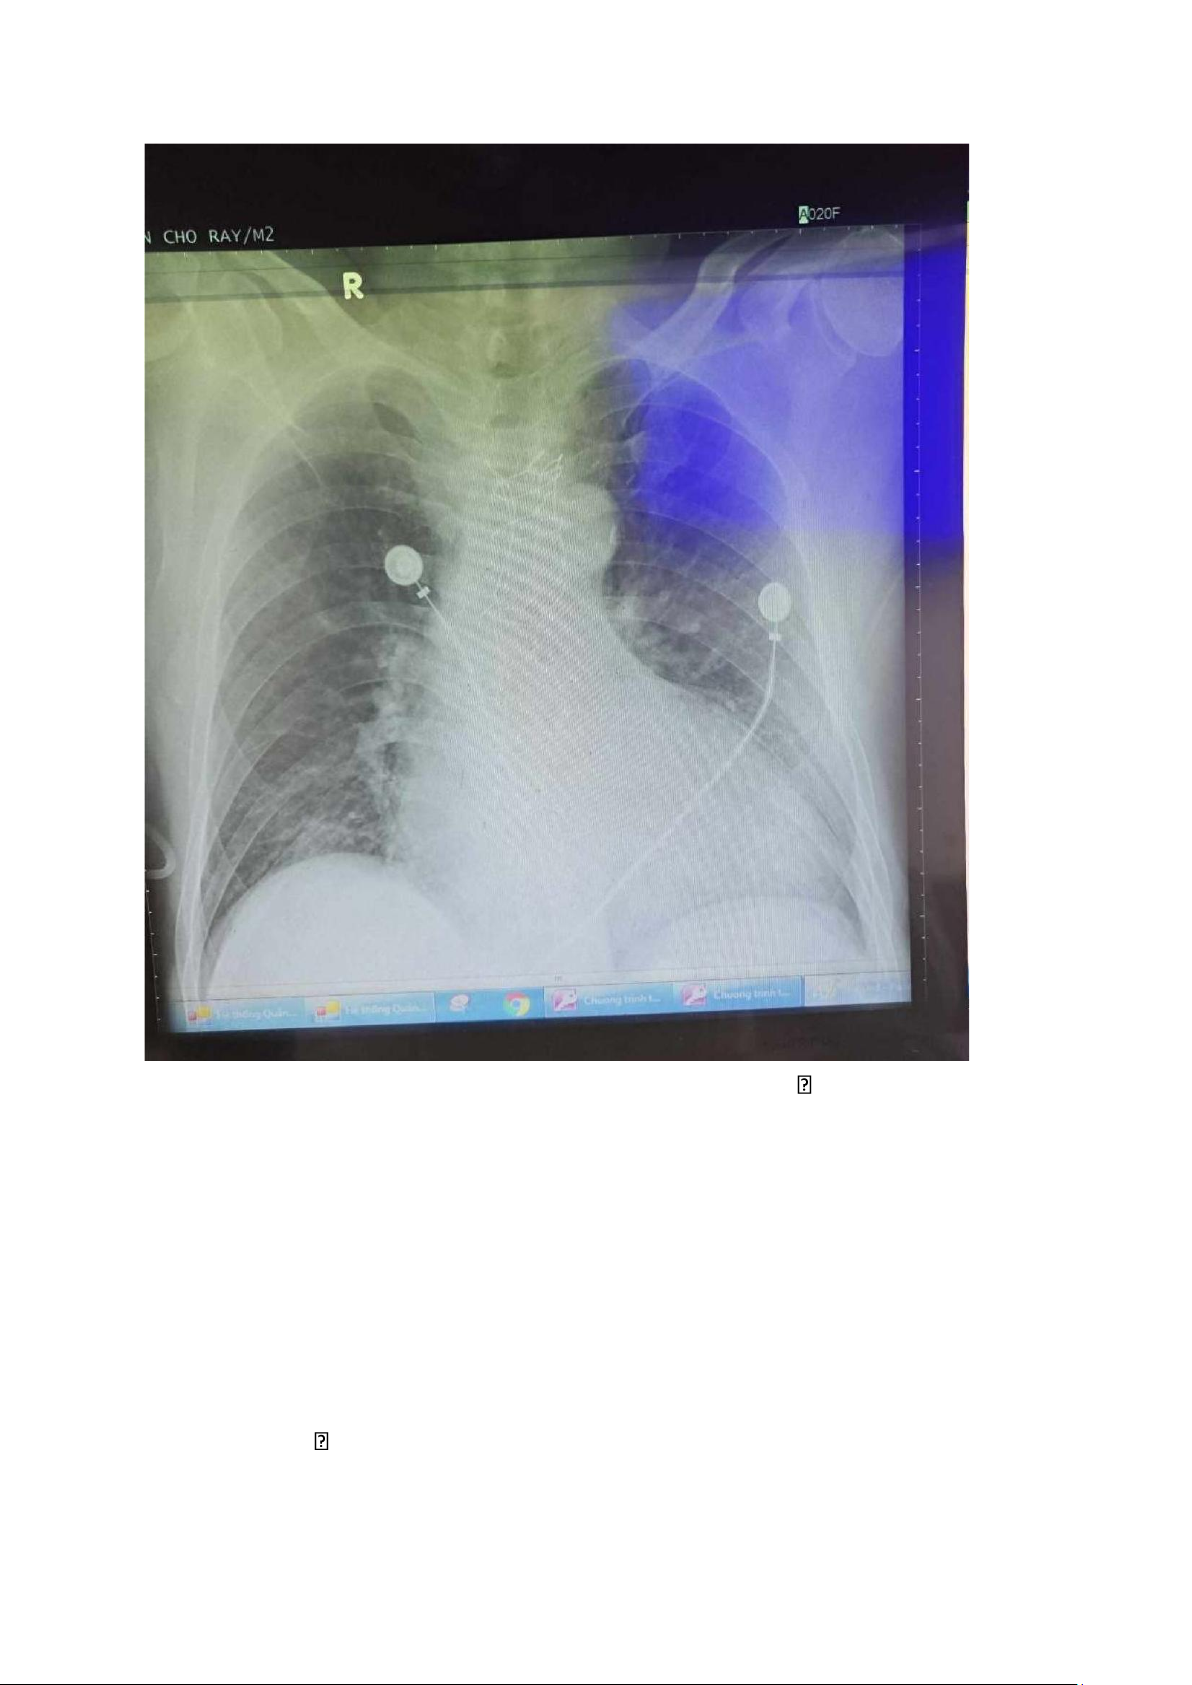

3. XQ ngực thẳng (cấp cứu) lOMoAR cPSD| 45470709

Phim nằm, xoay T, hít đủ sâu, cường độ tia mềm có thể đánh giá quá

mức các tổn thương hình mờ

- Không ghi nhận tổn thương thành ngực, vòm hoành và màng phổi 2 bên bình thường

- Bóng tim to, góc tâm hoành không xác định nghĩ do tổn thương

phổi gây xóa bờ, không thấy hình ảnh lớn nhĩ T, không lớn nhĩ P,

cung động mạch chủ trong giới hạn bình thường, tăng tuần hoàn phổi thụ động 2 bên

- Tổn thương dạng đám mờ không đồng nhất, giới hạn không rõ, ở

½ dưới phổi T, xóa bờ trái tim, không co kéo các cấu trúc lân cận nghĩ đông đặc lOMoAR cPSD| 45470709

Kết luận: bóng tim to, tăng tuần hoàng phổi 2 bên, hội chứng đông

đặc ½ dưới phổi trái phù hợp lâm sàng và ECG có lớn thất T,

phù hợp bệnh cảnh suy tim. Không thấy hình ảnh phù

phổi cấp nghĩ do tuyến dưới đã xử trí thở máy và vận mạch 4. Sinh hóa máu Xét nghiệm 11h52 17/9/2023 16/9/2023 10h16 Glucose 144 232 AST 50 43 ALT 80 51 Bilirubin TP 0.37 Bilirubin TT 0.15 Bilirubin GT 0.22 BUN 21 26 Creatinin 1.57 1.32 eGFR 46.88 57.81 Hs Troponin 2647 I 7h sau : 2777 Na+ 141 133 K+ 4.0 3.1 Cl- 107 93 Magnesium NT-proBNP 286.63 Cholesterol 102 mg/dl HDL- 19 mg/dl Cholesterol LDL- 38.9 mg/dl Cholesterol Triglycerid 393 mg/dl lOMoAR cPSD| 45470709 PT (giây) 10.8 11.9 APTT (giây) 28.9 36.5 rAPTT 1.11 1.4 INR 1.03 1.14 FIB 3.11